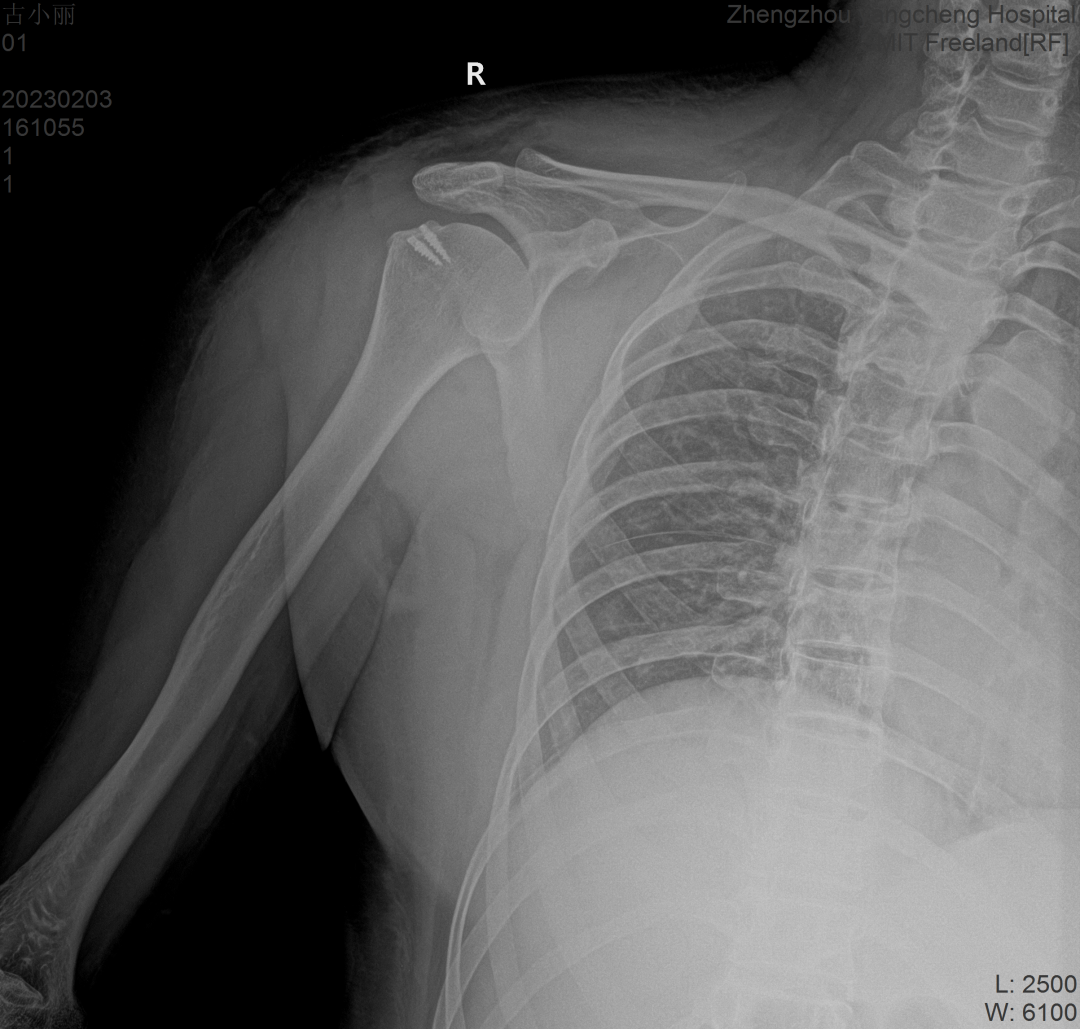

經(jīng)檢查診斷

右側(cè)肩袖損傷

損傷程度較嚴(yán)重

右肩部壓痛活動受限

右肩關(guān)節(jié)岡上肌肌腱全層斷裂